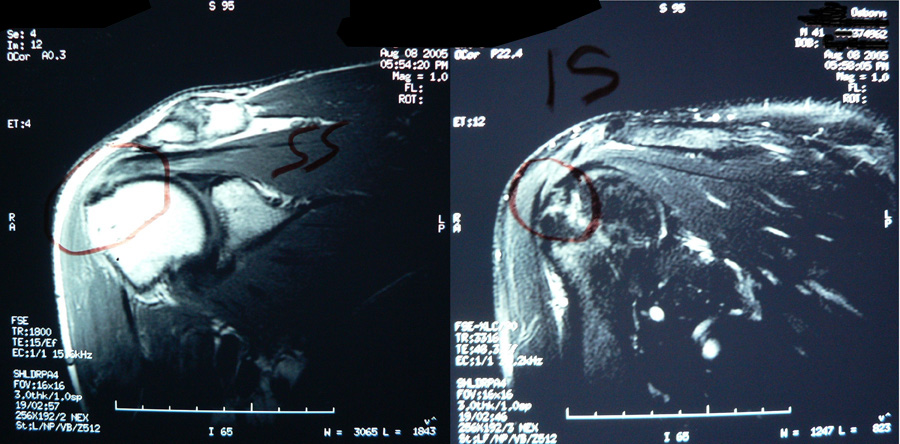

This patient presented with shoulder pain that interfered with work and exercise. The visible fluid-filled cysts on the “Before" MRIs are from chronically injured rotator cuff tendon roots.

The patient underwent treatments of a highly specialized fine-needling technique pioneered by Dr. Tallman.The follow-up MRI was done 2 months after his 6th treatment. He was released with a pain-free, full range of motion with unrestricted activities.